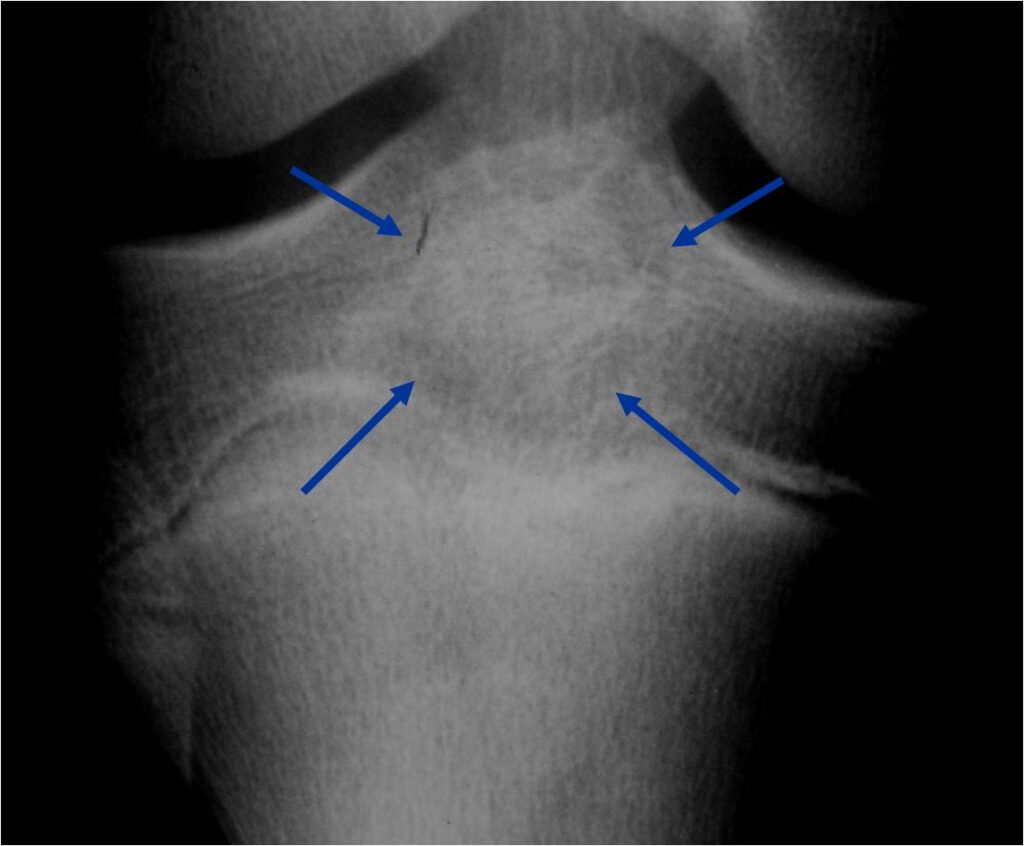

Radiographic Presentation

- Presents as a highly defined/well circumscribed geographic oval/round lytic defect

- Surrounded by rim of sclerotic bone

- Usually in epiphyseal region

- Lesion ranges from 3 cm to 6 cm diameter

- Usually radiolucent

- May have fine trabeculae and irregular calcifications

Plain x-ray appearance:

- Geographic lytic lesion IA/IB margin of sclerosis

- Usually Eccentric more often than Central in the bone

- Rarely expansile (rarely penetrates the cortex)

- Calcified chondroid matrix 30%-50% of cases

- Often better detected with a CT Scan

- Periosteal Reaction 30-50% of cases

- Usually occurs in Adjacent Diaphysis/Metaphysis since epiphysis is intraarticular and not surrounded by periosteum